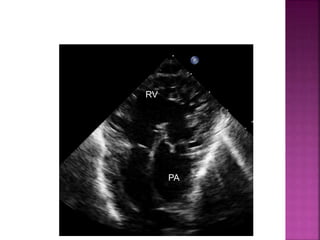

DELINEATE : sub pulmonary VSD , Over ride of

Pulm trunk over VSD, Absent PS, coexistence

of sub aortic stenosis, coarc Ao, and PDA

• size in relation to the diameter of the pulmonary artery

• presence and severity of a subpulmonary obstruction

• subcostal coronal and parasternal long axis planes

RV

PA